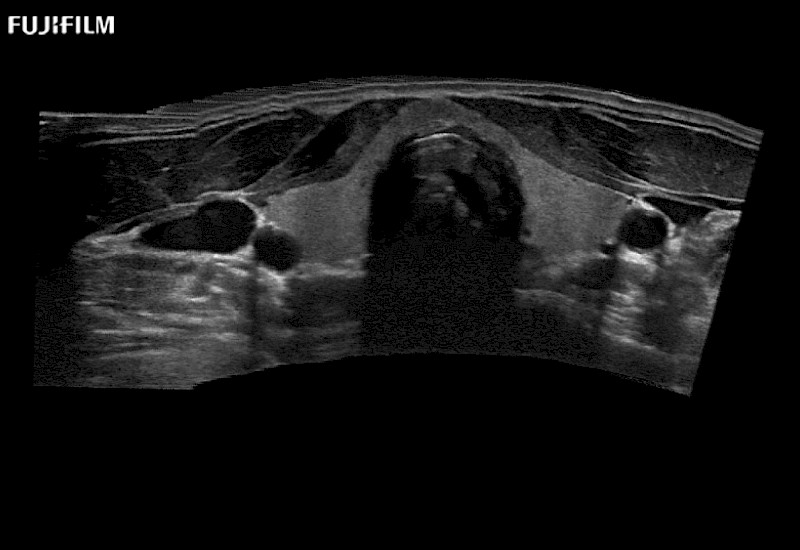

Our dedication to Surgical Oncology allows us to offer superior image quality, outstanding system reliability and intuitive use of cutting edge technology.